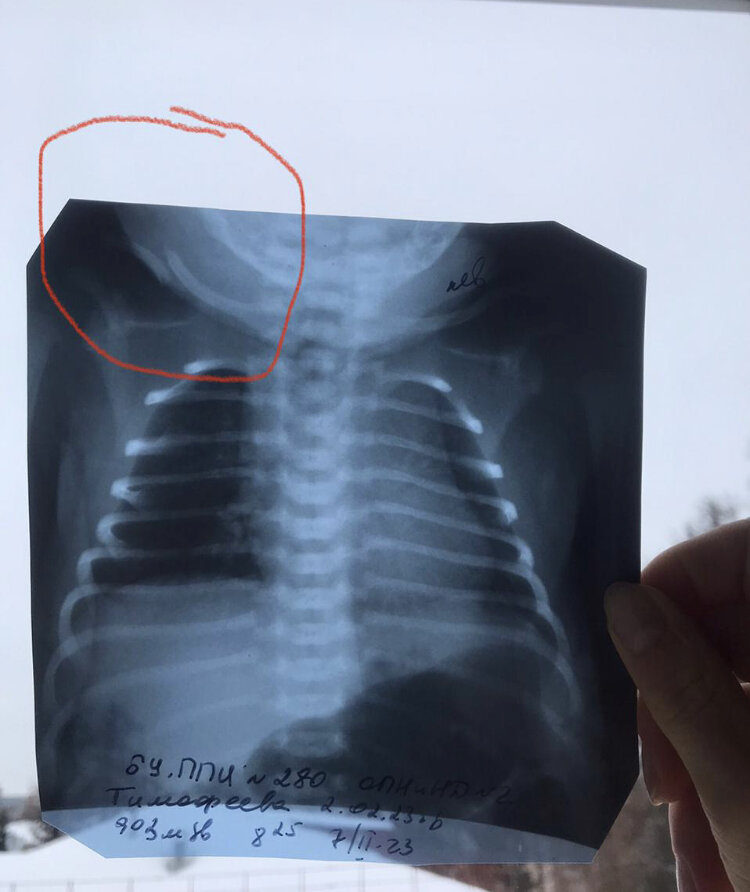

- X-rays: The primary diagnostic tool for clavicle fractures, providing clear images of the bone’s alignment and any displacement

Sometimes the bone is broken enough to create an angle between the broken ends, which causes a deformity along the bone. Usually with a broken collarbone the pain and swelling are severe and there may be a visible deformity. Often there is pain at the site of the fracture with any attempt to move the arm. The only way to verify if there is a fracture is to get an X-ray of the area.

- Take X-rays of the injured area to confirm a broken bone. X-rays can also show exactly where the break is, how bad it is and whether any other bones broke.

- Imaging tests -X-rays – an x-ray will define the break: the number of pieces and the degree of separation of the fragments. X-rays of the shoulder will be done to check for additional injuries (eg. scapula fracture).